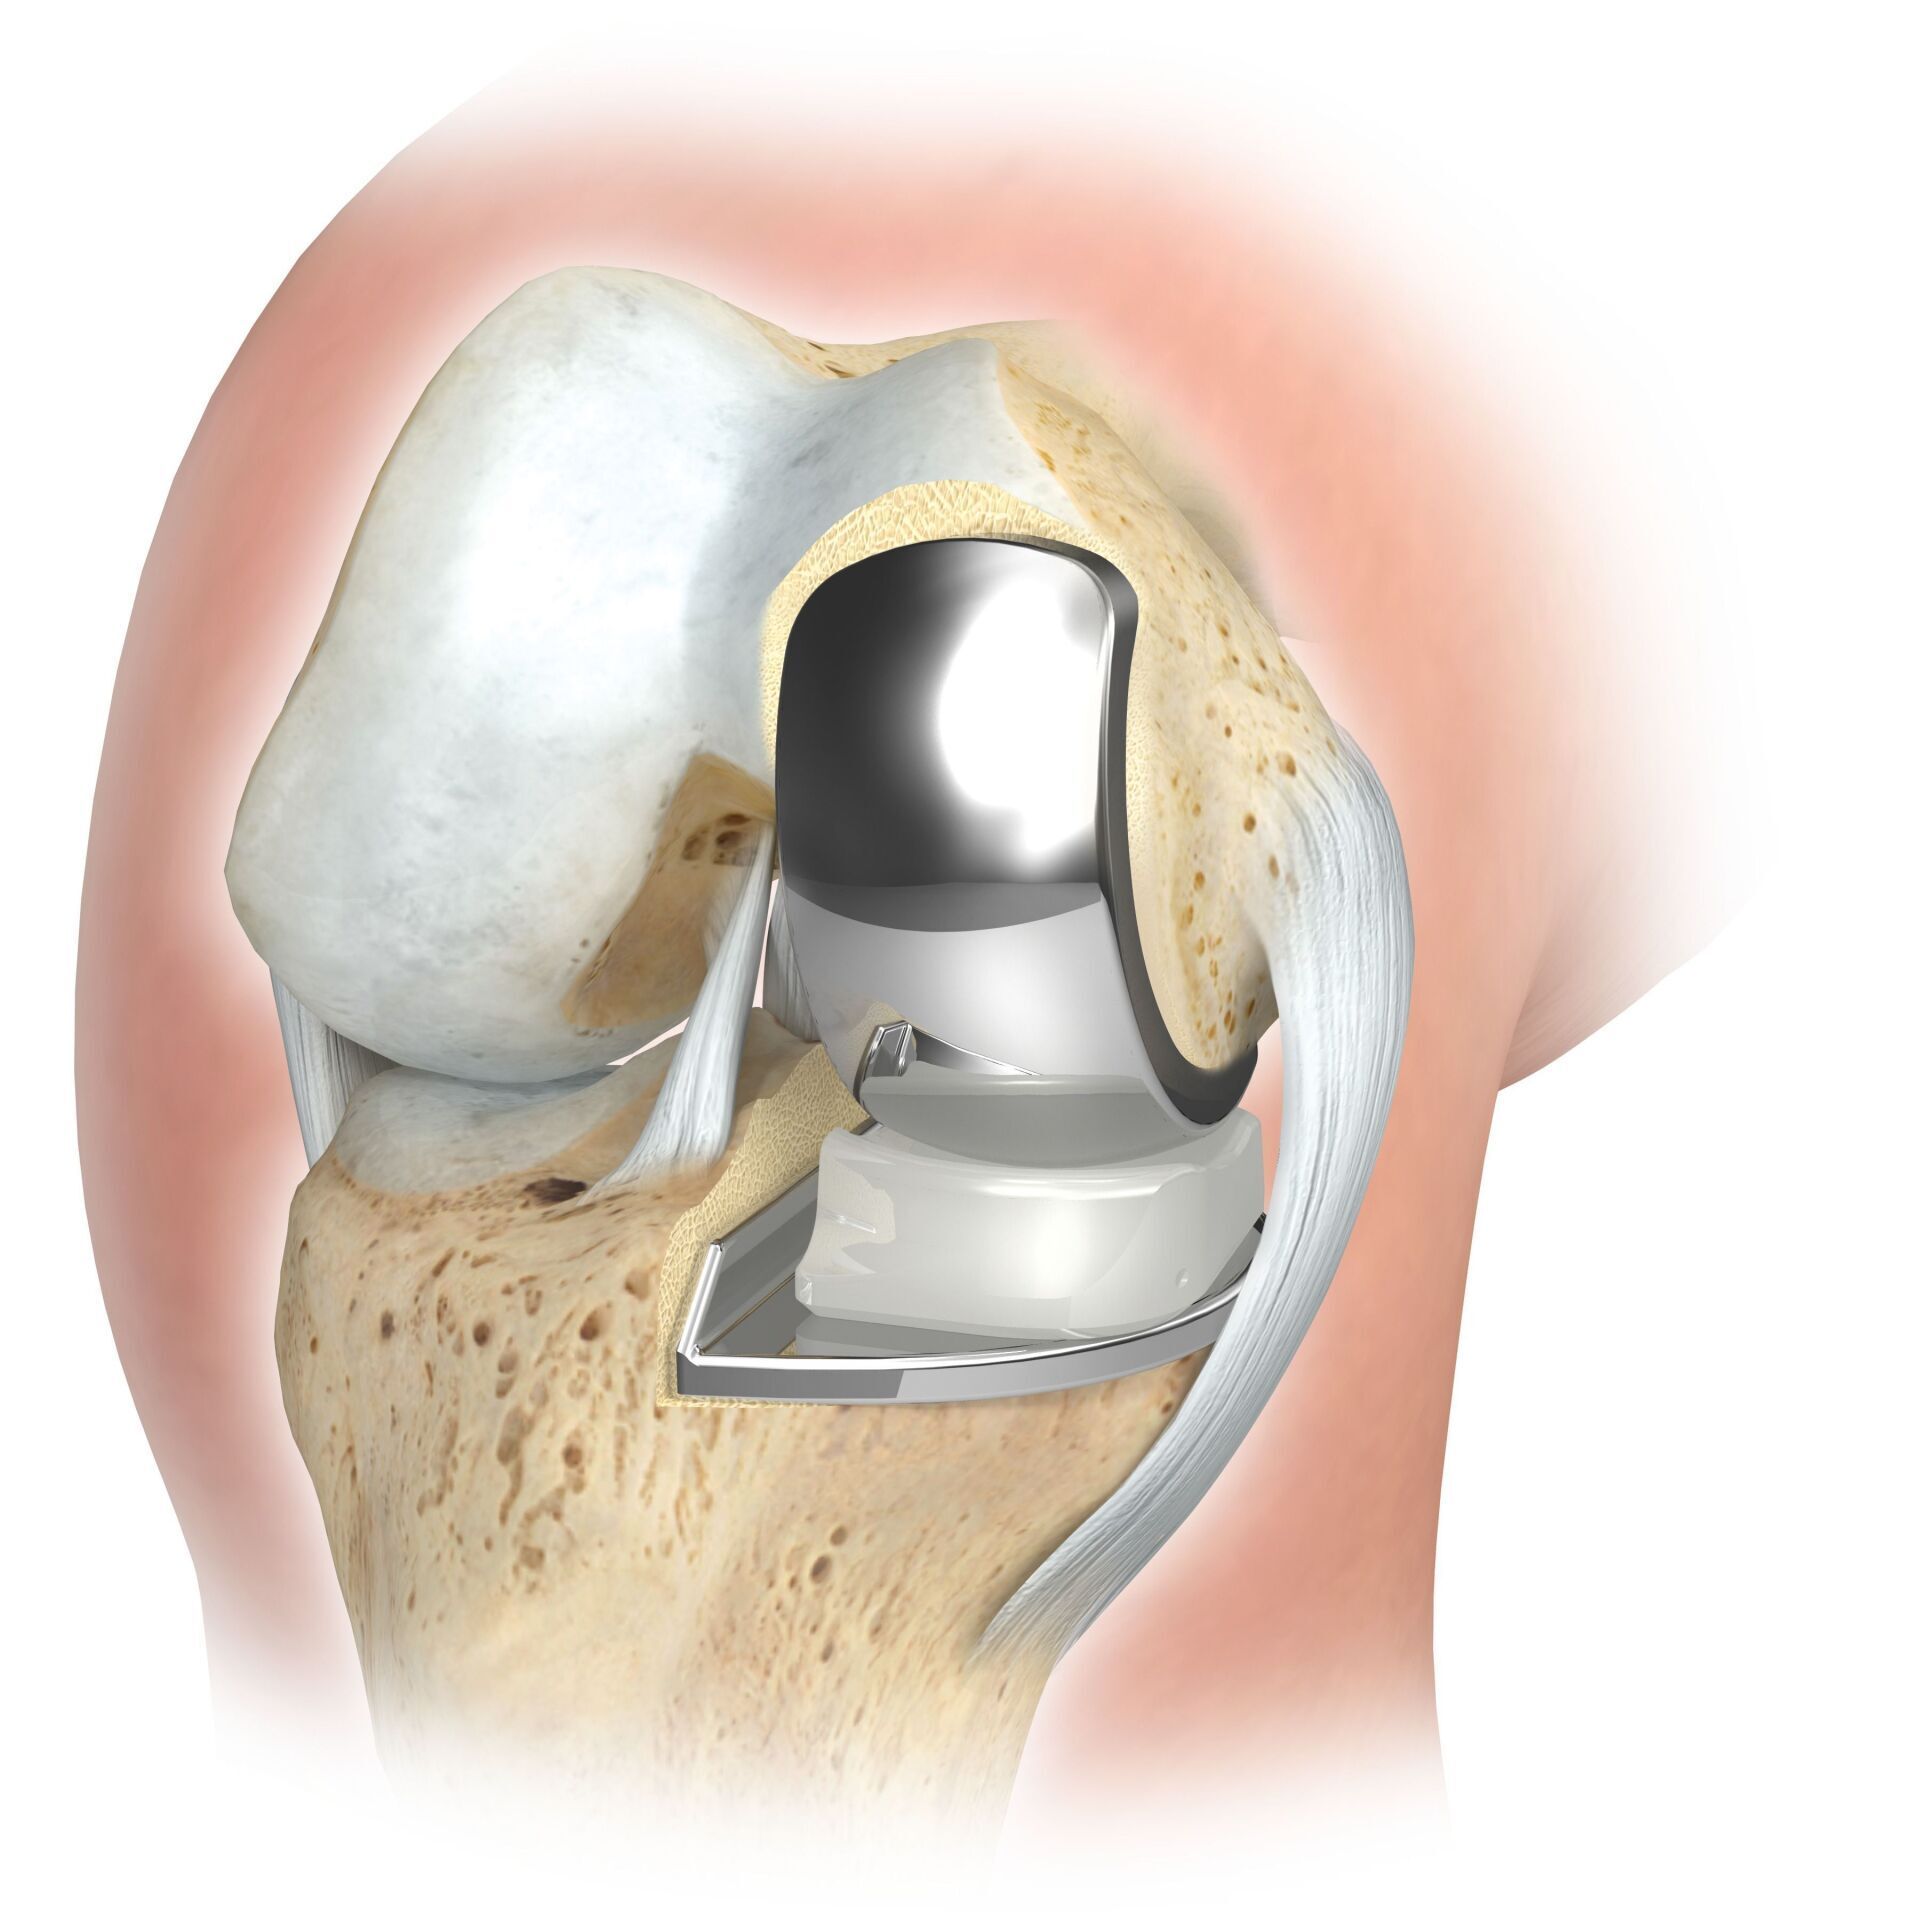

PROTHÈSE À GLISSIÈRE

L'arthroplastie partielle de l'articulation du genou est possible dans toutes les zones de l'articulation, mais elle est le plus souvent réalisée à l'intérieur de l'articulation du genou et est souvent appelée familièrement prothèse de traîneau. Semblable à la prothèse complète, le cartilage défectueux est remplacé par une nouvelle surface et un inlay en plastique est inséré entre les deux. Pour une prothèse partielle, toutes les structures ligamentaires, en particulier les ligaments croisés, doivent être en grande partie intactes.